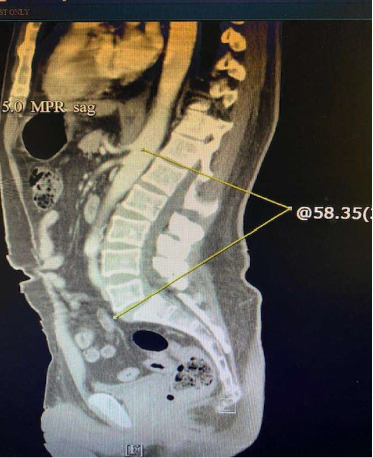

简介:僵硬人综合征(SPS)是一种罕见的神经系统疾病,其特征是肌肉僵硬、痉挛、特定的肌电图表现和谷氨酸脱羧酶水平升高。病人的症状和体征对全科医生和专科医生来说是具有挑战性的。病例报告:我们报告一例56岁男性,有1型糖尿病病史,伴有严重的胸部、腹部和腰痛;严重的心动过速;行走困难的患者在10个月的时间里看了不同的医生,但没有任何明显的改善。由于腹痛,他在此期间体重明显下降。多项研究,包括腹部和整个脊柱的计算机断层扫描和磁共振成像,上下胃肠道(GI)内窥镜检查和心导管插入术,均无显著性。患者出现严重的腹部和胸部疼痛,弥漫性腹肌僵硬,以及严重的心动过速。他的肌酸激酶和乳酸水平也升高。广泛的感染、心脏和胃肠道检查均为阴性。根据病史、临床检查和谷氨酸脱羧酶的高滴度,诊断为SPS。他对口服安定、巴氯芬和加巴喷丁反应良好,并接受了5天的静脉免疫球蛋白治疗。结论:对于反复出现心动过速、腹痛、胸痛的患者,应考虑SPS作为鉴别诊断的依据。对于非神经科医生来说,熟悉这种疾病是很重要的。

Introduction: Stiff person syndrome (SPS) is a rare neurological disorder marked by muscle stiffness, spasms, specific electromyographic findings, and elevated levels of glutamate acid decarboxylase. Patients' symptoms and signs can be challenging for general practitioners and specialists. Case report: We present a case of a 56-year-old man with a history of type 1 diabetes with episodes of severe chest, abdominal, and low back pain; severe tachycardia; and difficulty with walking who was seen by different physicians over a period of 10 months without any significant improvement. He had significant weight loss during this period due to abdominal pain. Multiple studies, including computerized tomography and magnetic resonance imaging of the abdomen and entire spine, upper and lower gastrointestinal (GI) endoscopies, and cardiac catheterization, were unremarkable. The patient presented at our facility with severe abdominal and chest pain, diffuse abdominal muscle rigidity, and periods of severe tachycardia. He also had elevated creatine kinase and lactate levels. Extensive workup for infectious, cardiac, and GI processes was negative. The patient was diagnosed with SPS based on history, clinical examination, and an exceedingly high titer of glutamic acid decarboxylase. He responded well to oral diazepam, baclofen, and gabapentin, and he received a 5-day course of intravenous immunoglobulin therapy. Conclusion: In patients presenting with recurrent tachycardia, abdominal pain, and chest pain, SPS should be considered in the differential diagnosis. It is essential for non-neurologists to be familiar with this disorder.